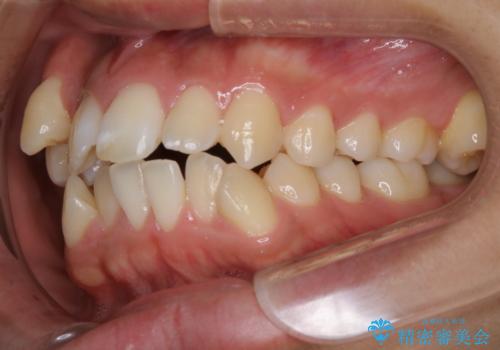

- オーディションで歯並びを指摘されたことから一念発起して矯正治療を行う事にした方です。

親知らずと、前から4番目の歯を抜歯してワイヤー装置による矯正治療を行いました。

人前に出ることが多いため、当初は目立たない装置をご希望されていましたが、歯の移動距離が大きいため効率よく歯を動かせる表側の装置での治療をお勧めしました。すれ違ってしまっていた奥歯もしっかり治すことができました。